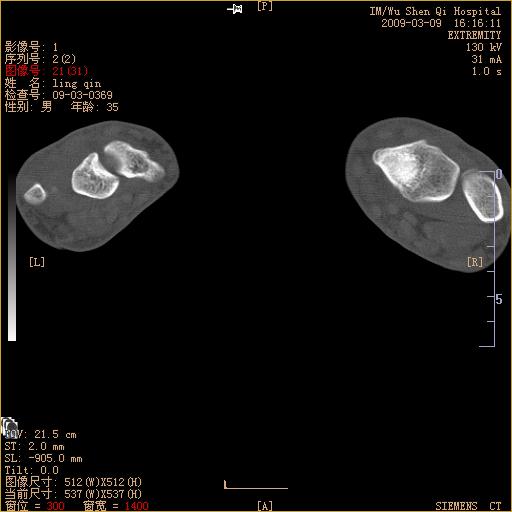

标题: CT18570:右手外伤10余天

请上传x线平片。舟状骨骨折可能大。

腕部有骨折、脱位,骨科面对ct片如何采取措施?三维一下。

请上传x线平片,腕骨多骨骨折

舟状骨骨折。

左侧舟骨及桡骨茎突骨折,第一掌骨基底部好像也有骨折,建议上传平片